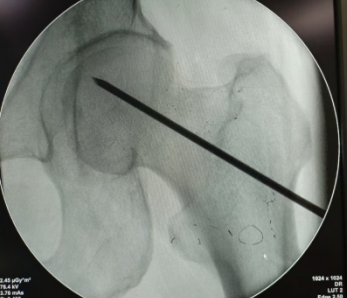

邹国耀主任对王先生的病情进行了详细评估,并组织科室医疗团队开展病例讨论。根据王先生情况,制定了髋关节镜下滑膜清理+髓芯减压死骨刮除后植骨+生物陶瓷棒置入的保髋手术治疗方案:

最终,在邹国耀主任的指导下,陈椿荣副主任医师团队成功为王先生开展了保髋手术治疗。术后经「医生—护士—康复医师」一体化康复,王先生很快出院,下肢功能逐渐恢复。